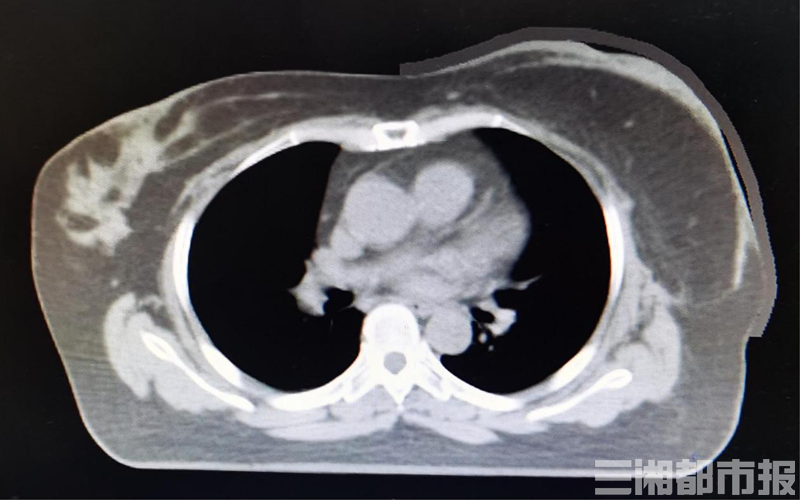

(上/常规组织补偿物与体表的空气间隙;下/3D打印组织补偿物与体表的控件间隙明显缩小)

(实施3D打印组织补偿物技术实例)